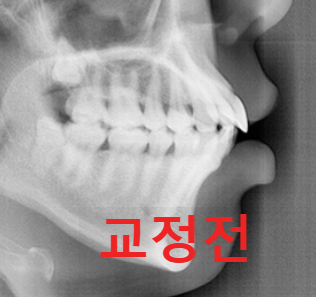

2. 두개골(머리뼈) 방사선 촬영

3. 치아 방사선 촬영